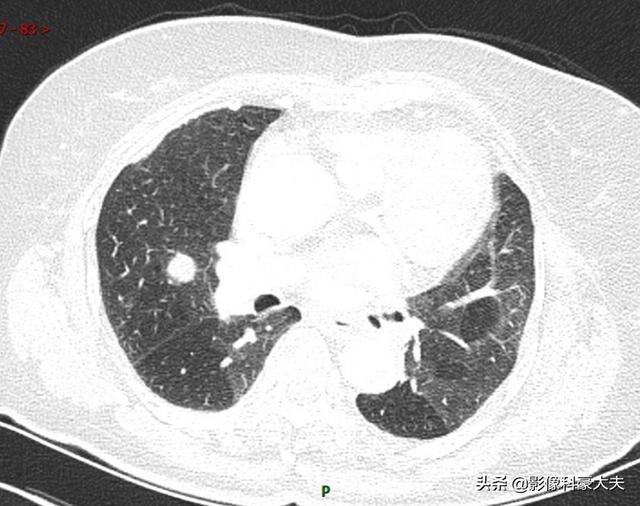

この女性患者は、3ヵ月前にはなかった1.1cmの肺結節があり、病理結果は転移性肺腺癌であった。